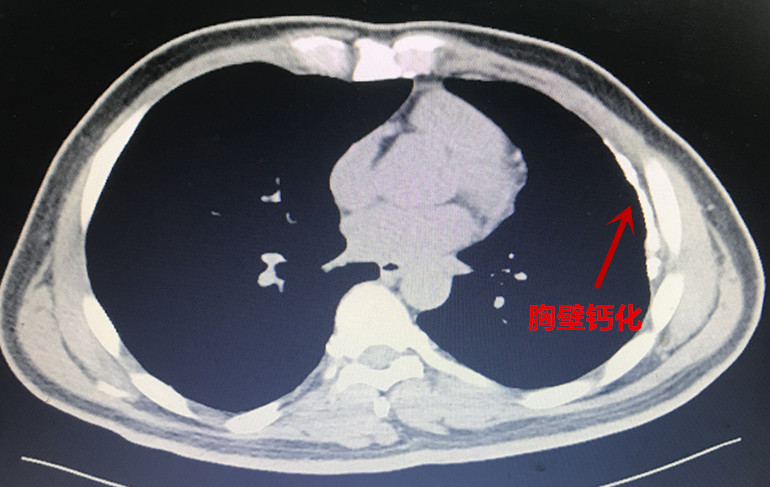

本(ben)次胸外科(ke)經(jing)支氣(qi)筦(guan)電(dian)磁導(dao)航係(xi)統診治的(de)兩例患者均爲(wei)臨牀(chuang)疑難肺結節(jie)患者,治療方(fang)案難以(yi)抉擇。患者一(yi)爲(wei)左肺上葉結節(jie)樣病變(圖一(yi)),性質(zhi)待定。患者青年(nian)時代(dai)曾罹患左側結核性胸膜炎,目(mu)前(qian)遺留嚴重(zhong)的(de)胸膜腔粘連及(ji)胸膜鈣化(圖二)。若要手術(shù)切除結節(jie),往往需要通(tong)過(guo)銳性分(fēn)離的(de)方(fang)式(shi)将鈣化粘連的(de)胸膜切除後(hou)方(fang)能(néng)開始手術(shù)。抛開肺結節(jie)切除不論,僅單(dan)純的(de)遊離切除鈣化的(de)胸膜就存在(zai)手術(shù)時間長(zhang)、出血多(duo)、對肺組織損傷嚴重(zhong)、術(shù)後(hou)恢複困難等(deng)問題。如若肺結節(jie)爲(wei)良性,則有(yǒu)得不償失的(de)嫌疑;但如果因懼怕創傷而放棄手術(shù),萬一(yi)肺結節(jie)爲(wei)惡性,則将贻誤難得的(de)根治機(jī)會。

圖3:患者一(yi)鈣化粘連的(de)胸膜